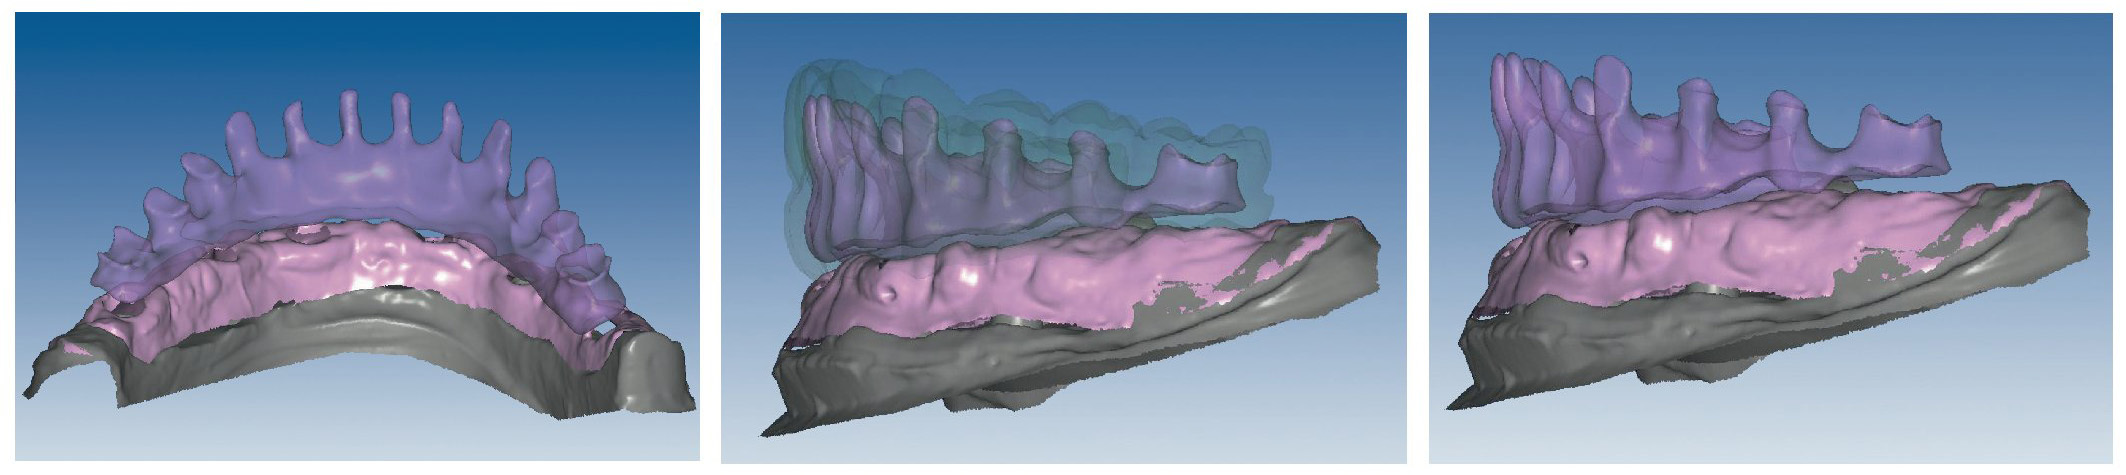

Mediante el uso de un escáner óptico de luz estructurada, los protocolos CAD registran los primeros datos relativos al modelo maestro con las correspondientes posiciones de implante (figs. 87 y 92). En el siguiente paso tiene lugar la digitalización de la planificación, previamente realizada en cera de escaneo matificada, de la restauración definitiva (figs. 88, 90 y 93). La subsiguiente conciliación de los datos mediante el uso del software de diseño dental permite al protésico planificar virtualmente el resto del procedimiento (figs. 89 y 91, 94 a 96) a partir del diseño de las estructuras (figs. 97 y 98).

Figs. 94 a 95. Planificación CAD de la estructura del maxilar inferior, en representación lingual y vestibular.

Figs. 96 a 98. El diseño definitivo de la estructura del maxilar inferior, desde distintas perspectivas.